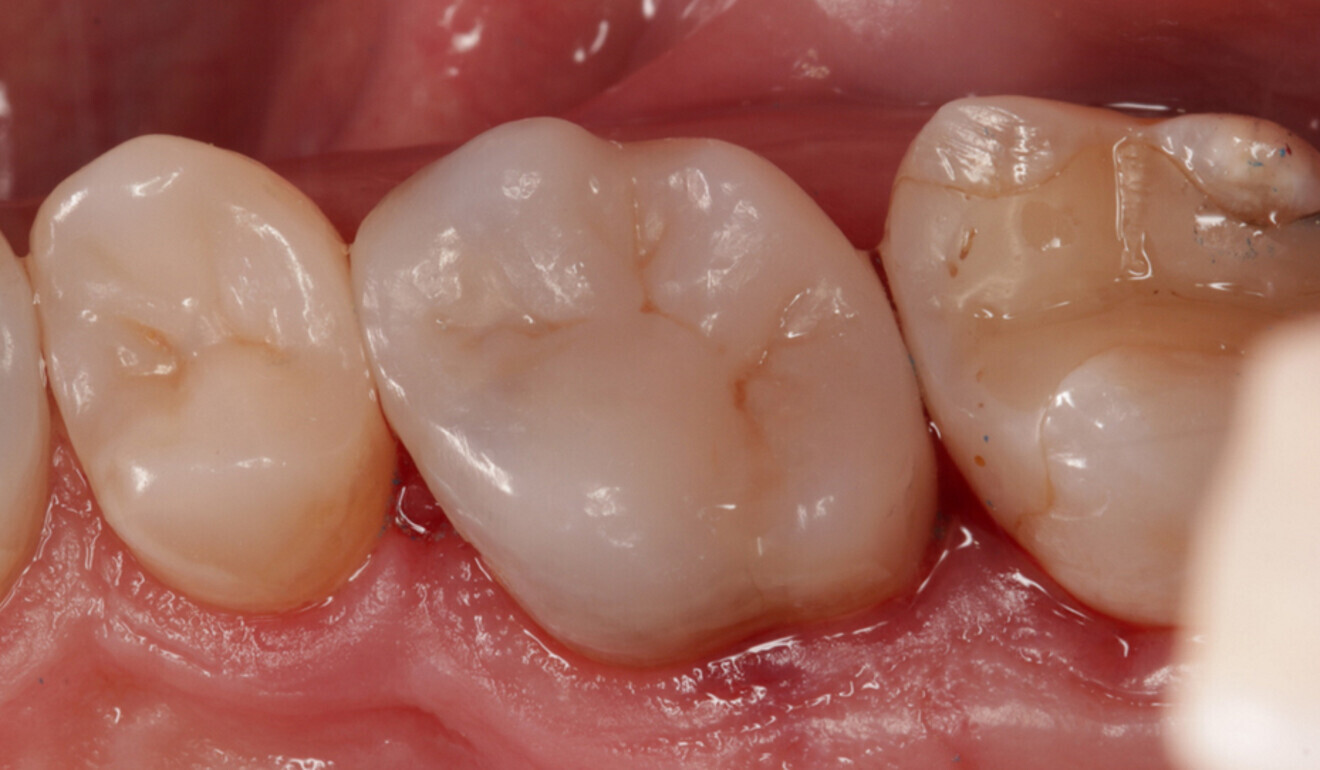

Fig. 21: Final effect, palatal view. (Image: Kuraray Noritake Dental)